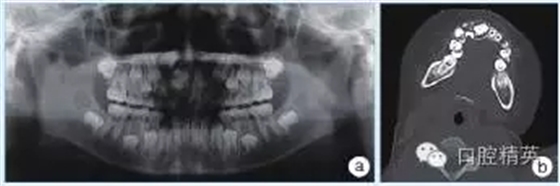

輔助檢查:全頜曲面斷層片顯示左側(cè)下頜骨體部可見類圓形高密度影,周圍可見低密度影環(huán)繞(圖1a);CT顯示:左側(cè)下頜骨體部呈膨脹性骨質(zhì)改變,局部骨皮質(zhì)變薄,內(nèi)伴高密度骨質(zhì)硬化影,邊界尚清晰,周圍軟組織腫脹(圖1b)。

圖1 a:全頜曲面斷層片;b:CT影像